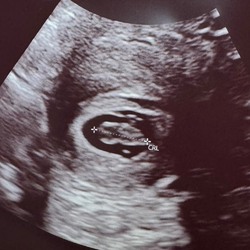

Ik heb het 2 keer kunnen opvangen , er naar gekeken en afscheid van genomen . Kon het op beide momenten nie begraven of dragen omdat mijn dochtertje in de buurt was . Sommige mensen hebben de kans om het te begraven en een plantje erboven te zetten . Ik heb een kadertje met een echo .

Wij hebben het in een mooie ronde kistje bij ons in de kast waar hij in ligt in een waterzakje met 3 gekleurde regenboogrozen voor ons elk 1 er staat een budha bij van mijn man een sterrenkind engeltje van me moeder en een hartje met de tekst carried for a moment loved for a life time van me schoonmoeder. Hierbij de 2 mooie duidelijke echo foto's en de foto van zijn handje erbij. Zo is hij nog bij ons. Begraven konden wij niet gevoelsmatig, zk heeft iedereen weer een eigen mooie ideeën.